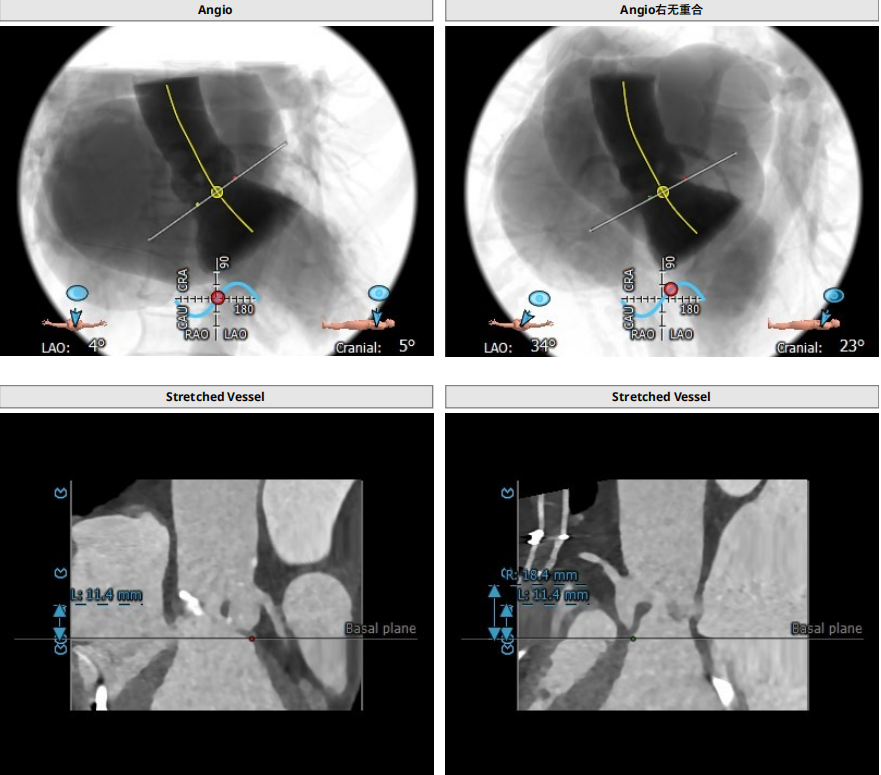

三叶瓣轻度钙化,右无可见钙化脊,瓣叶可见增厚,右冠高度可,左冠开口层面可见瓣叶,升主动脉未见明显扩张,法式窦及窦管交界稍小,两侧股动脉入路可,二尖瓣机械瓣置换术后。瓣环平均径23.7mm,LVOT26.8mm,STJ24.9mm,RCA18.4mm,LCA11.4mm。